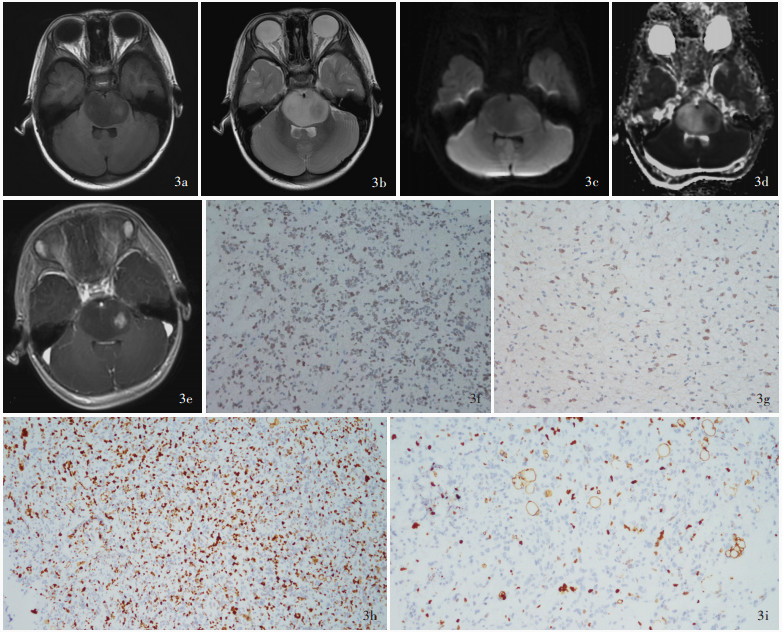

目的: 探讨儿童后颅窝常见肿瘤的影像学诊断与鉴别诊断方法,并按照先定位诊断再定性诊断的思路,基于DWI是否弥散受限提出儿童后颅窝常见肿瘤的诊断流程图。方法: 共纳入2021年1月至2024年1月在复旦大学附属华山医院予以手术切除的118例儿童后颅窝肿瘤患者,均行头部CT和MRI检查,并据此进行术前定位和定性诊断,分别以术中所见和术后病理学检查为诊断“金标准”,判断术前定位诊断和定性诊断的准确性;再基于DWI是否弥散受限提出儿童后颅窝常见肿瘤的诊断流程图。结果: 共118例后颅窝肿瘤患儿定位和定性诊断为第四脑室肿瘤计41例,包括髓母细胞瘤27例、毛细胞型星形细胞瘤7例、室管膜瘤5例、脉络丛乳头状瘤1例、形成菊形团的胶质神经元肿瘤1例;脑干肿瘤38例,包括弥漫性中线胶质瘤,H3 K27变异型24例、毛细胞型星形细胞瘤5例、海绵状血管瘤3例、儿童型弥漫性高级别胶质瘤(倾向弥漫性中线胶质瘤,H3野生型)2例、节细胞胶质瘤2例、非典型性畸胎样/横纹肌样肿瘤1例、儿童型弥漫性低级别胶质瘤1例;脑桥小脑角肿瘤计9例,包括毛细胞型星形细胞瘤3例、胆脂瘤2例、髓母细胞瘤1例、弥漫性中线胶质瘤,H3 K27变异型1例、毛细胞黏液型星形细胞瘤1例、尤文肉瘤1例;小脑肿瘤计30例,包括毛细胞型星形细胞瘤15例、髓母细胞瘤7例、海绵状血管瘤2例、室管膜瘤1例、儿童型弥漫性低级别胶质瘤1例、儿童型弥漫性高级别胶质瘤(倾向弥漫性中线胶质瘤,H3野生型)1例、胚胎发育不良性神经上皮肿瘤1例、错构瘤1例和肾外横纹肌样瘤小脑转移瘤1例。定位诊断,术前CT的定位诊断准确率为93.22%(110/118),MRI的定位诊断准确率达100%(118/118)。定性诊断,74例(62.71%)患儿定性诊断准确,23例(19.49%)诊断笼统,21例(17.80%)诊断错误。儿童后颅窝肿瘤的影像学鉴别诊断集中于髓母细胞瘤、毛细胞型星形细胞瘤、室管膜瘤、弥漫性中线胶质瘤,H3 K27变异型。位于脑干外的髓母细胞瘤、毛细胞型星形细胞瘤和室管膜瘤的DWI弥散受限发生率分别为100%(35/35)、4%(1/25)和5/6,3种肿瘤之间差异有统计学意义(Z=-5.601,P=0.000);位于脑干的弥漫性中线胶质瘤,H3 K27变异型和毛细胞型星形细胞瘤的DWI弥散受限发生率为79.17%(19/24)和1/5,两种肿瘤之间差异亦有统计学意义(Fisher确切概率法:P=0.038)。结论: 儿童后颅窝肿瘤早期诊断较为困难,DWI是鉴别诊断的重要依据,基于DWI是否弥散受限提出的儿童后颅窝常见肿瘤诊断流程图有望提高术前诊断的准确性。

Objective: To investigate the imaging diagnosis and differential diagnosis methods for common tumors in the posterior fossa of children, and to propose a flow chart for the diagnosis of common tumors in the posterior fossa of children based on the limited diffusion of DWI according to the idea of localization diagnosis followed by qualitative diagnosis. Methods: A total of 118 pediatric patients with posterior fossa tumors who underwent surgical resection in Huashan Hospital, Fudan University from January 2021 to January 2024 were enrolled, and all of them underwent head CT and MRI examinations, and preoperative localization diagnosis and qualitative diagnosis were carried out accordingly. Then, based on whether DWI was diffusion limited, a flow chart for the diagnosis of common tumors in the posterior fossa of children was proposed. Results: A total of 118 children with posterior fossa tumors were localization and qualitatively diagnosed, including 41 cases of fourth ventricular tumors, including medulloblastoma (27 cases), pilocytic astrocytoma (7 cases), ependymoma (5 cases), choroid plexus papilloma (one case), and rosette-forming glioneuronal tumor (RGNT, one case). There were 38 cases of brainstem tumors, including 24 cases of diffuse midline glioma, H3 K27-altered, 5 cases of pilocytic astrocytoma, 3 cases of cavernous hemangioma, 2 cases of pediatric-type diffuse high-grade glioma (prone to diffuse midline glioma, H3 wild type), 2 cases of ganglio glioma, one case of atypical teratoid/rhabdoid tumor (AT/RT), and one case of pediatric-type diffuse low-grade glioma. There were 9 cases of cerebellopontine angle (CPA) tumors, including 3 cases of pilocytic astrocytoma, 2 cases of cholesteatoma, one case of medulloblastoma, one case of diffuse midline glioma, H3 K27-altered, one case of pilomyxoid astrocytoma, and one case of Ewing sarcoma. There were 30 cases of cerebellar tumors, including 15 cases of pilocytic astrocytoma, 7 cases of medulloblastoma, 2 cases of cavernous hemangioma, one case of ependymoma, one case of pediatric-type diffuse low- grade glioma, one case of pediatric-type diffuse high- grade glioma (prone to diffuse midline glioma, H3 wild type), one case of dysembryoplastic neuroepithelial tumor (DNT), one case of hamartoma, and one case of extrarenal rhabdomyomatoid tumor cerebellar metastases. Localization diagnosis, the accuracy of preoperative CT was 93.22% (110/118), while the accuracy of preoperative MRI was 100% (118/118). Qualitative diagnosis, 74 cases (62.71%) had accurate qualitative diagnosis, 23 cases (19.49%) had general diagnosis, and 21 cases (17.80%) had wrong diagnosis. The imaging differential diagnosis of posterior fossa tumors in children focuses on medulloblastoma, pilocytic astrocytoma, ependymoma, and diffuse midline glioma, H3 K27-altered. The incidence of limited diffusion of DWI in medulloblastoma, pilocytic astrocytoma and ependymoma outside the brainstem was 100% (35/35), 4% (1/25) and 5/6, and the difference among the three tumors was statistically significant (Z =-5.601, P = 0.000). The incidence of limited diffusion of DWI in diffuse midline glioma, H3 K27-altered and pilocytic astrocytoma in the brainstem was 79.17% (19/24) and 1/5, and the difference between the two tumors was also statistically significant (Fisher's exact possibility: P = 0.038). Conclusions: The early diagnosis of posterior fossa tumors in children is difficult, and DWI is an important basis for differential diagnosis.